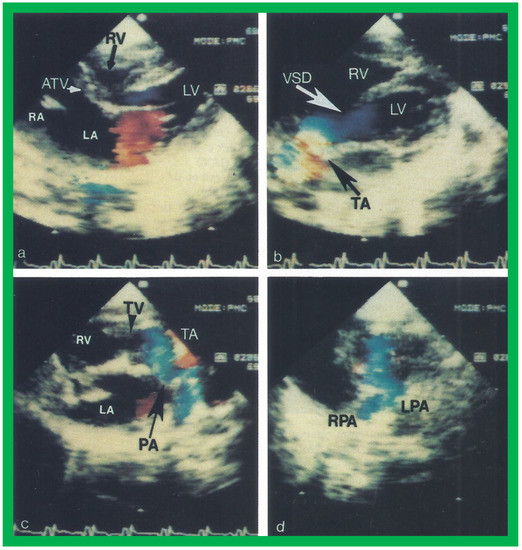

Figure 13. Two dimensional echocardiographic video frames demonstrating (a) an atretic tricuspid valve (ATV) between the right atrium (RA) and right ventricle (RV), (b) a large subtruncal ventricular septal defect (VSD), (c) thickened and somewhat domed truncal valve (TV) leaflets, and (d) the origin of the pulmonary artery (PA) from the posterior aspect of the truncus arteriosus (TA). LA, left atrium; LV, left ventricle. Reproduced from Rao PS, et al. Am Heart J 1991;122:829–835 [31].

Applsci 11 09472 g013

Figure 14. Video frames from a two dimensional echocardiographic and color Doppler study demonstrating (a) an atretic tricuspid valve (ATV) between the right atrium (RA) and right ventricle (RV), and blood flow from the left atrium (LA) into the left ventricle (LV) across the mitral valve. The RV (arrow) is very small and hypoplastic. (b) LV and RV with a large ventricular septal defect (VSD) below the truncus arteriosus (TA). Turbulent flow across the truncal valve suggests truncal valve stenosis. (c) The origin of the pulmonary artery (PA) from the TA by color flow (arrow), and (d) the division into right (RPA) and left (LPA) pulmonary arteries from the PA in a short-axis view. TV, truncal valve leaflets. Reproduced from Rao PS, et al. Am Heart J 1991;122:829–835 [31].

Applsci 11 09472 g014

The relationship of the great arteries is examined next in order to classify them into various types, as mentioned above. The relationship of the great arteries (Figure 2, top) is established by following the vessels arising from the ventricles until the pulmonary artery (PA) bifurcation or aortic arch. In Type I patients with normally related great arteries, the aorta arises from the LV (Figure 10) and in Type II patients with transposition of the great arteries, the PA arises from the LV (Figure 11; Figure 12). In Type II patients, the blood vessel arising from the LV should be traced to demonstrate its branching into the right and left PAs (Figure 11; Figure 12). In Type III patients, it may be a little more difficult to assign the great artery relationship and, sometimes, other imaging studies, including angiography, may be needed to define the great artery relationship. In Type IV with truncus arteriosus, the limited data suggest that this can be performed by echocardiography (Figure 13; Figure 15). In the example shown [31], the atretic tricuspid valve (Figure 13a and Figure 14a), VSD (Figure 13b and Figure 14b), hypoplastic RV (Figure 14a), single vessel (truncus) arising from the heart (Figure 13c,d, and Figure 14c,d), and origin of the PA and its division into branch PAs (Figure 13d, and Figure 14c,d) were demonstrated.